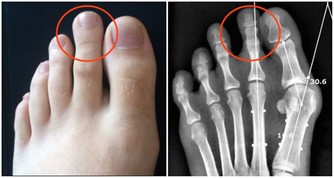

5.肢體麻木

患者常有明顯的手指麻木感,導致運動不靈敏。